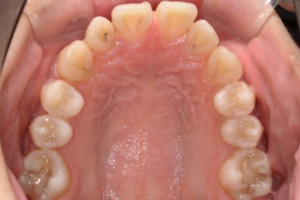

PROCESS

半年

下の前歯が上あごの歯ぐきに当たるほど噛み合わせが深く、そのことが原因で上顎歯列の正中にすき間(正中離開)が生じていました。部分矯正ですき間を無理やり閉じても、噛み合わせが深いままでは治療後の再発リスクが高くなります。そのため全体矯正で奥歯の噛み合わせを整え、噛み合わせを浅くしつつ前歯を並べました。正中離開は戻りやすい傾向があるので、再発を防ぐため固定式リテーナーを推奨しています。